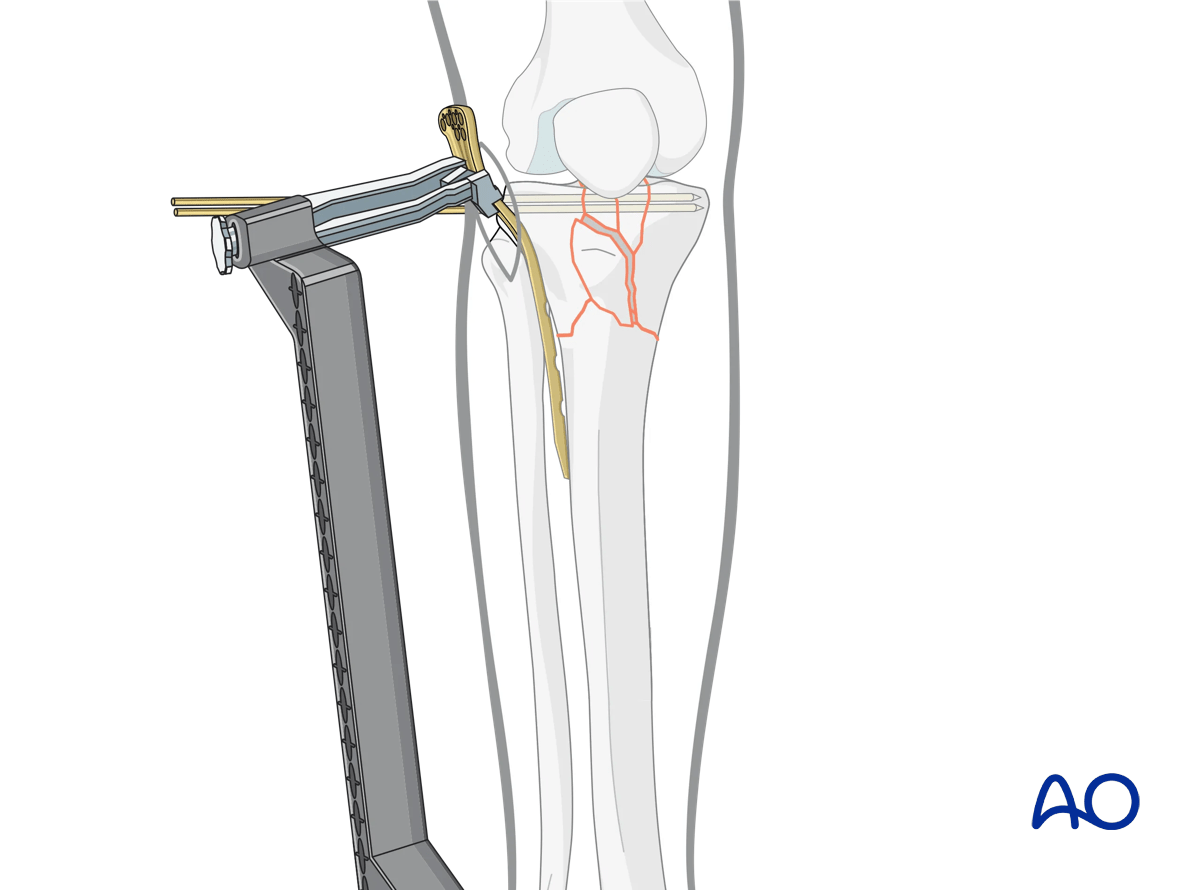

Indirect reduction with external devices

If manual reduction is unsuccessful, indirect reduction can be achieved with the use of external fixation, and/or a universal distractor.

The pin insertions should be planned carefully to avoid conflict with the subsequent placement of screws of the plate used for fixation of the fracture.

If the proximal fragment is small, place the proximal Schanz pins for either the universal distractor or external fixator into the femur, in order to avoid difficulties.